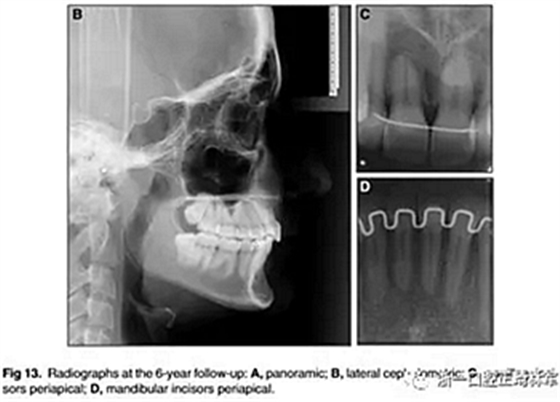

6年后治療結(jié)果保持穩(wěn)定(圖11,圖12 ; 圖13)??梢杂^察到穩(wěn)定的間隙關(guān)閉,正常的覆蓋和覆合,上下牙中線一致,微笑美觀。建議完美替代了拔除的側(cè)切牙。正畸治療后進(jìn)行牙齒美白。

頭顱測量疊加(圖14)顯示,面部特征在治療過程中發(fā)生變化,并在6年的隨訪評估中保持穩(wěn)定。上頜骨和下頜骨的區(qū)域疊加也表明治療期間的單純牙齒移動和骨骼穩(wěn)定性。在后續(xù)檢查中獲得并維持適當(dāng)?shù)母采w和覆蓋(表格)。